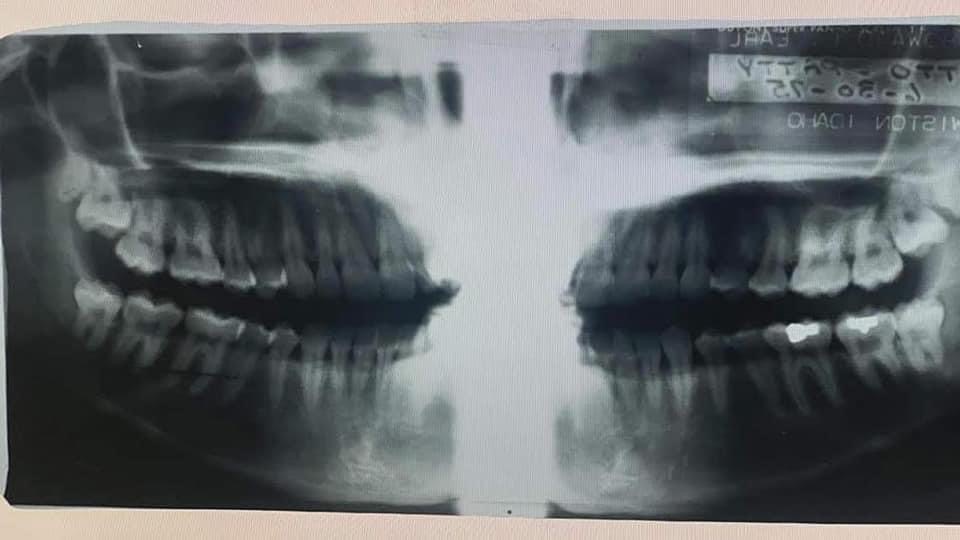

Patricia Otto's daughter still believes Finley Creek Jane Doe is her. Here are Patricia's last known dental x-rays and a written description of Jane Doe's dentals.

IMG_7058.JPG

IMG_7057.JPG

Patricia Otto's daughter still believes Finley Creek Jane Doe is her. Here are Patricia's last known dental x-rays and a written description of Jane Doe's dentals. View attachment 400998View attachment 400996

Namus doesn’t even have a correct record for my mother….how do they ever identify anyone? How many wisdom teeth are seen in the ONLY X-ray they have for my mother? 4. Yet they documented she has none. They can’t back that info up but refuse to change it.

Exactly. And that's a huge thing to not have documented it with at least a photograph. Why is there nothing to support this ME's reporting on several identifying key factors. Firstly, the x-ray and fcjd teeth totally match up. Every shape, angle and gap totally line up. Every tooth listed by ME on his list of fcjd is just as the x-ray clearly shows and Dane, with the exception of the upper right third molar. And that's already been explained since that's the likely tooth to be extracted and the reason this x-ray exists. And it's also clear the ME was confused on his own written note by stating unless Patty had only 3 third molars removed when fcjd clearly still had 3 third molars. Okay, he references seeing a note that Patty had all her third molars removed, where's that more? Who have him that note? Why is it not included in the report? Why was there no photo evidence of this alleged near full term baby?

@PattysVoice I'm confused about the dental information between your mom and FCJD. Dr. Nici Vance said that Patty had her 3rd molars (wisdom teeth) removed. FCJD still had 3 of 4 present. Dr. Vance also said that Patty had two amalgam fillings on Teeth 18, 19. FCJD also had 2 amalgam fillings but they were on Teeth 30, 31.

I saw new information that conflicts with Dr. Vance's opinion. Now it's believed both women had silver fillings on their teeth 30, 31. Patty had all 4 wisdom teeth in her last dental chart, but had trouble with the right upper wisdom tooth. That tooth is missing on FCJD. Was Dr. Vance's comparison wrong?

My speculation is that the written dental record for FCJD is the SAME information for a Doe found in Oregon less than 30 days prior. FCJD was never sent to Oregon State University for a proper dental record to be made. In 1986, the FBI asked Oregon to add the dental chart to the national database. They used the ME description. The ME completely discredits his record, when he rules my mother out and references the OTHER Doe. You have to see the autopsy photos to understand this is clearly my mother.